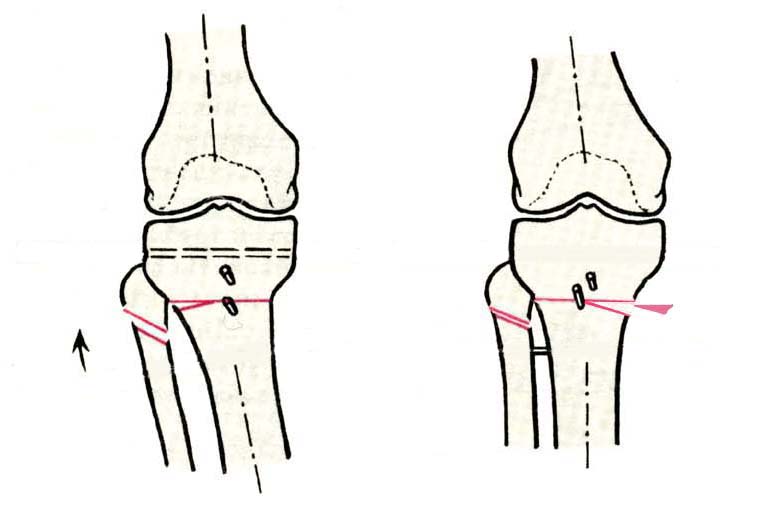

Дополнительными методами диагностики являлось измерение внутрикостного давления в зоне гипернагрузки и радионуклидные исследования нуклидами технеция. Применялись различные варианты остеотомий на различных сегментах. Для коррекции варусной-торсионной деформации:

высокие плюс, минус остеотомии большеберцовой кости,косая остеотомия малоберцовой. Для коррекции вальгусной деформации применялась плюс, минус надмыщелковая остеотомия бедренной кости. Фиксацию при высокой подмыщелковой остеотомии производили уникальной клинковой пластиной и тяговыми кортикальными винтами. Угол коррекции выставлялся

специальным угломером и направителем.

GBS> варусной-торсионной деформации: высокие плюс, минус остеотомии

GBS> большеберцовой кости,косая остеотомия малоберцовой.

Плюс, минус - это при одной операции? В смысле, и иссекали небольшой клин, и оставляли открытый с другой стороны?

>Плюс, минус - это при одной операции? В смысле, и иссекали небольшой

>клин, и оставляли открытый с другой стороны?

В зависимости от баланса связок, комбинировали (+-)остеотомии или производили полную

минус или плюс остеотомию